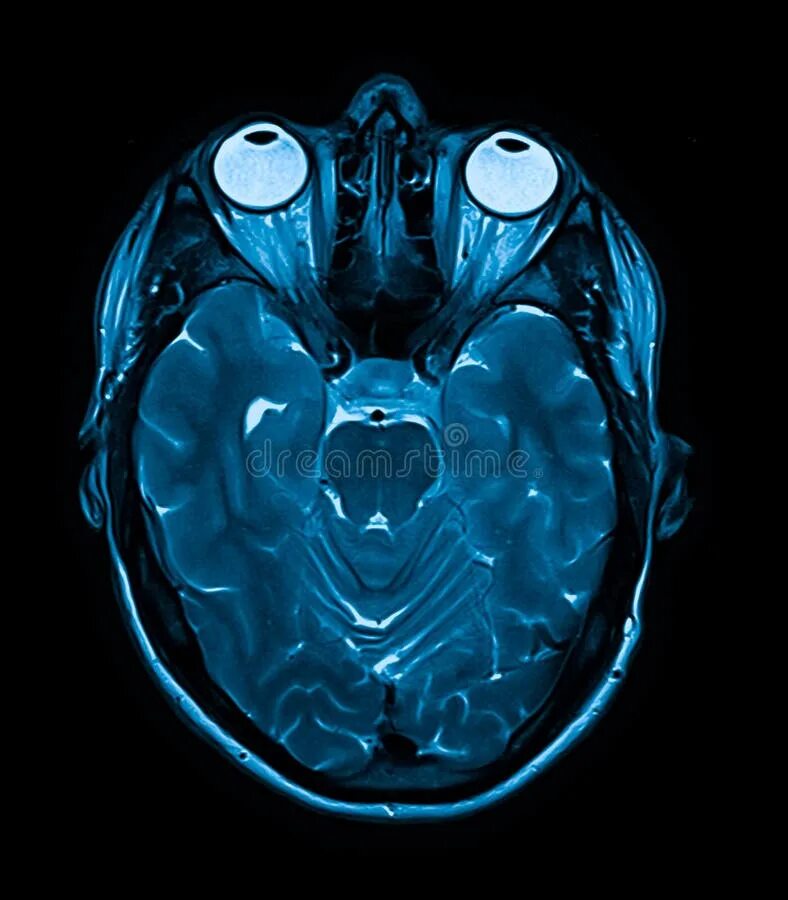

Мрт орбит и зрительных нервов